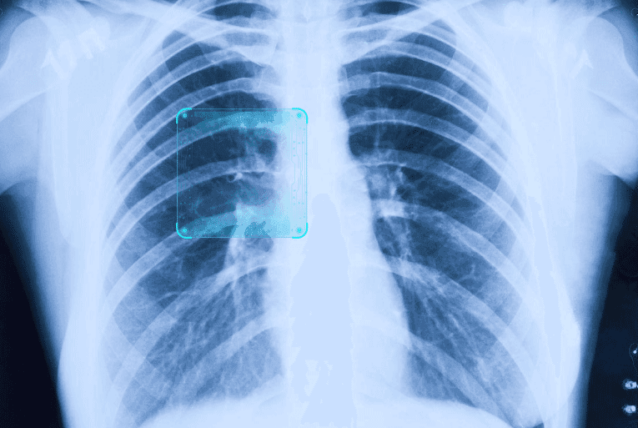

医疗诊断

帮助医生通过分析医学影像来诊断疾病

疾病诊断

影像诊断